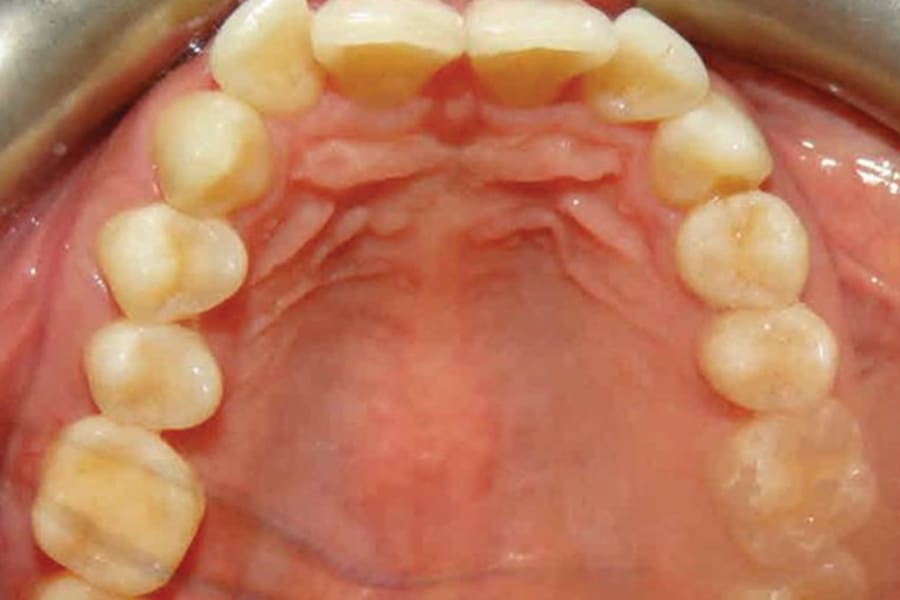

A 35-year-old woman presented with concerns of crowding, bruxism, and bite misalignment, which were associated with a class II malocclusion that would require a combination treatment of expansion, distalization, and molar derotation. ClearCorrect® aligner therapy (Straumann, clearcorrect.com) was selected as the primary modality, as the patient requested a non-invasive, esthetic treatment. The treatment plan was designed to be completed within 6 months of active aligner therapy. Class II elastics were prescribed, and the ClearCorrect FLEX case plan was chosen to allow for refinements, as needed. After comprehensive digital records were taken, the first set of aligners was delivered, engagers were bonded, and the patient was instructed to wear aligners on a 14-day cycle with full-time class II elastic wear. To enhance efficiency, more engagers were placed, including posterior attachments, to maximize control over molar distalization and anchorage. Interproximal reduction of 0.3 mm was performed in a few contacts at the initial appointment to facilitate space closure and alignment. Due to the complexity of the correction and the patient’s history of bruxism, a lower 3-3 bonded retainer was placed, and retainers were fabricated for both arches. The patient expressed a high level of satisfaction with the ClearCorrect aligner therapy, noting the comfort and esthetics of the aligners and the ability to achieve a fully corrected class II occlusion in just 6 months of treatment.